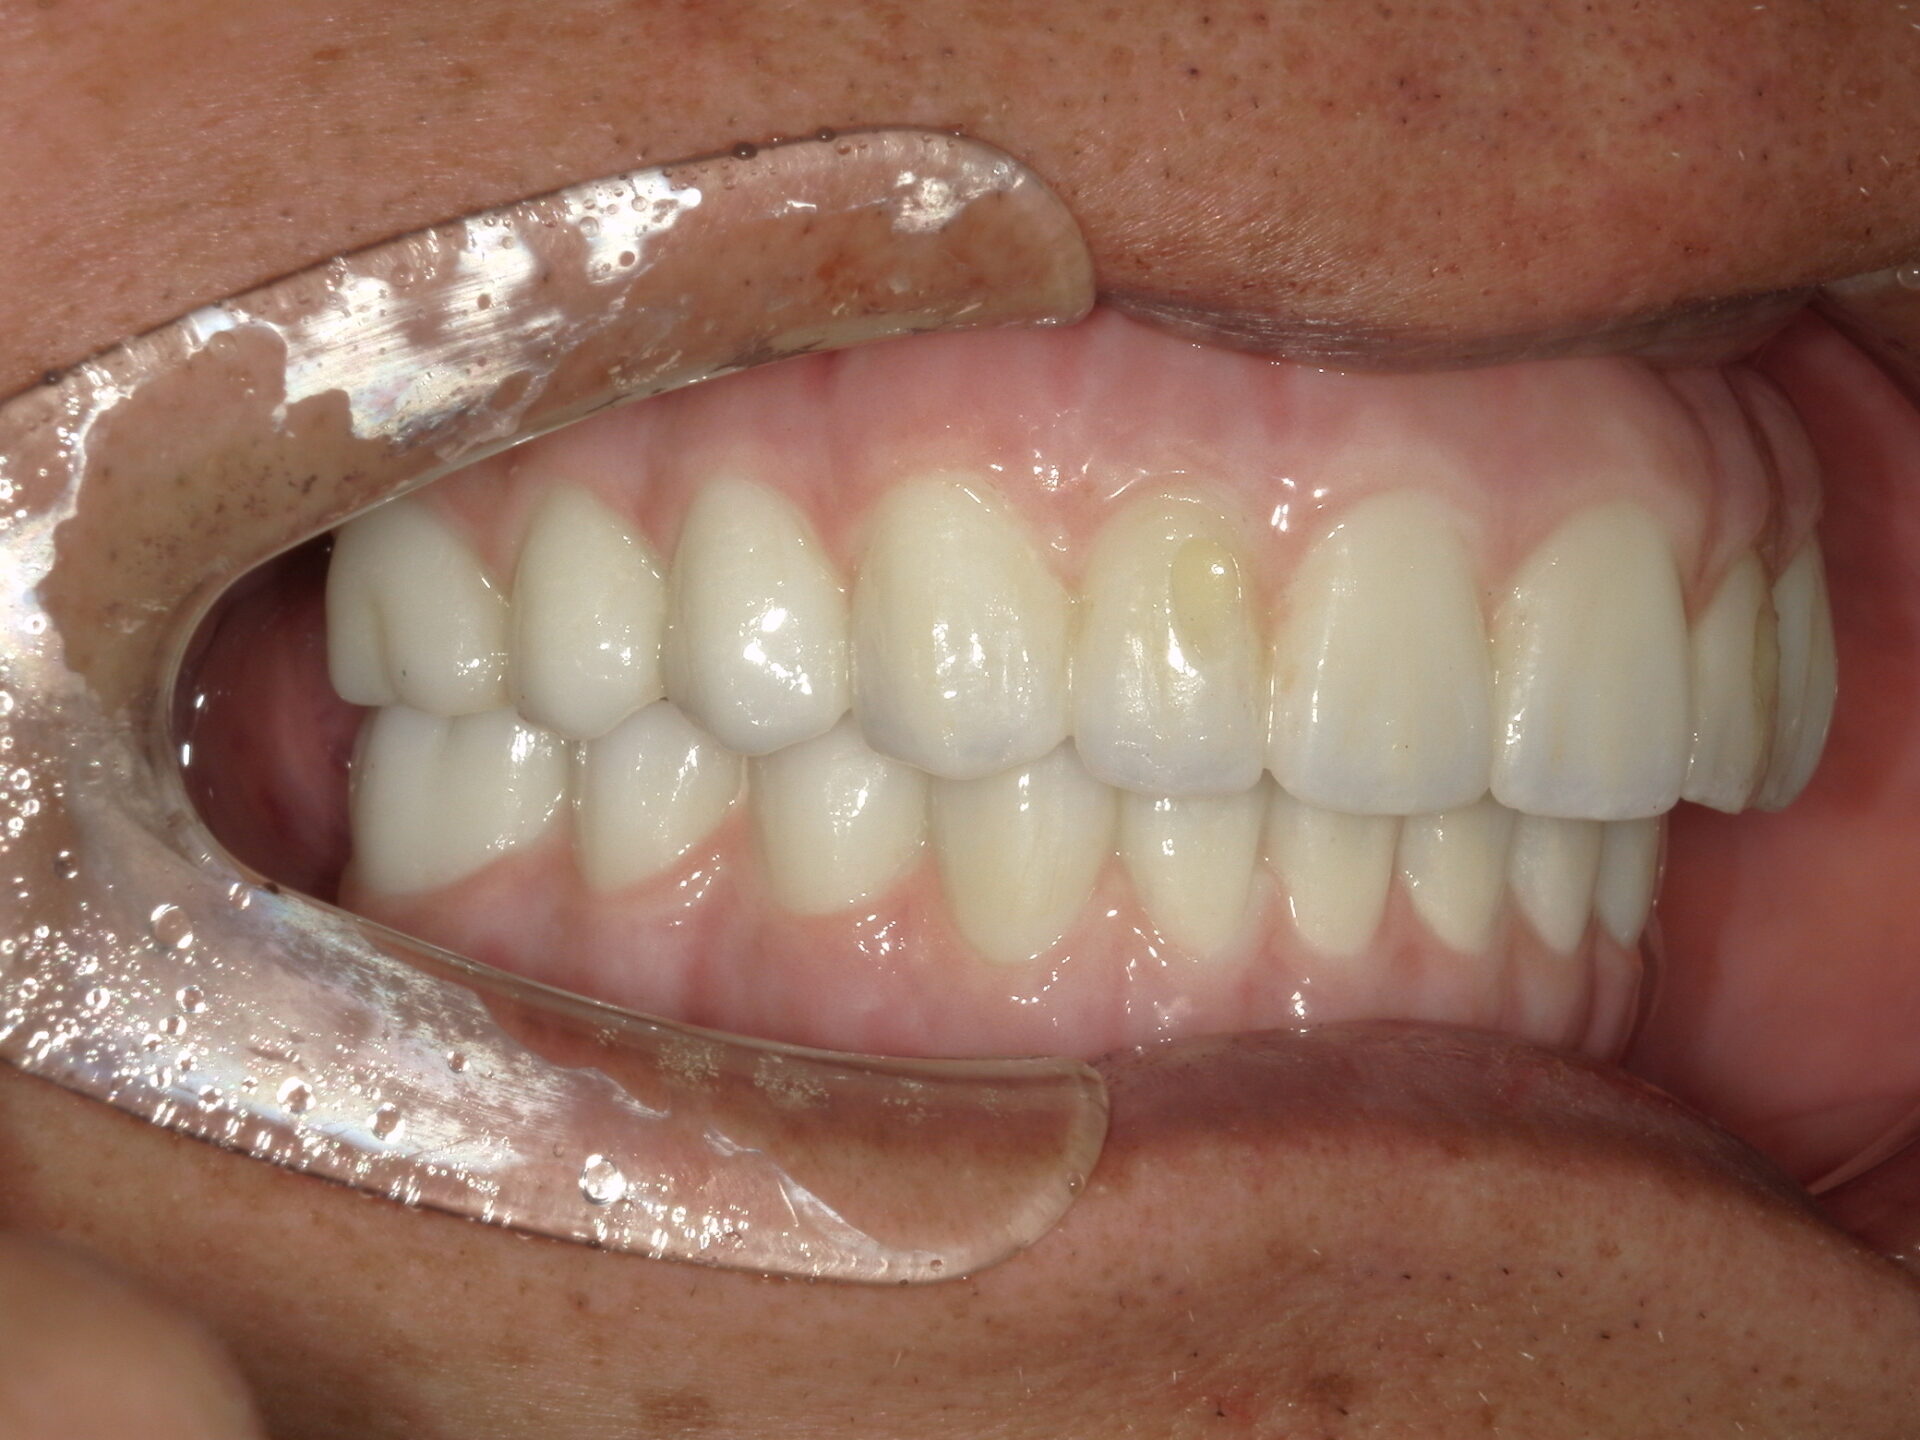

before

after

患者さんの年齢 50代 男性 症状 何も噛めない 治療内容 インプラント治療(オールオン4) 費用 費用900万(税抜) 治療期間・回数 治療期間2年・通院回数12回 メリット なんでも噛めるようになる 見た目が綺麗 デメリット・リスク 骨造成などで費用が増える場合がある - インプラント治療